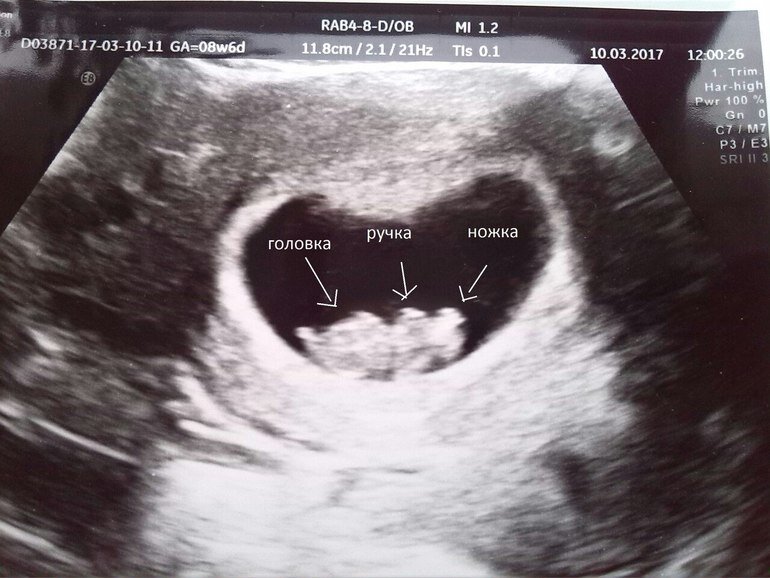

На 8 неделе беременности, придя с работы домой, я обнаружила в своём белье кровянистые выделения. Я сильно испугалась, впала в шок, легла на кровать и даже не моргала. К счастью муж вытащил меня из парализованного и состояния и повёз в больницу. Всю дорогу я молила, чтобы ничего страшного, чтобы малыш был жив, что такое бывает и всё хорошо. Но, когда меня положили на кушетку, чтобы сделать узи, всё стало понятно. Сердце не бьётся. Врач вот так просто мне это сказал: «Сердце не бьётся, можете одеваться». И удалился к медсёстрам, чтобы продолжить их весёлое обсуждение.